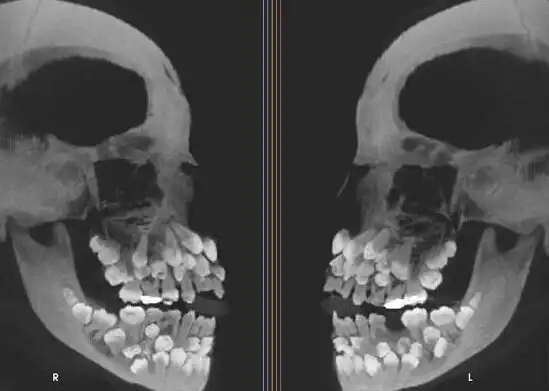

А это снимок человека с гипердонтией (аномалия числа зубов)